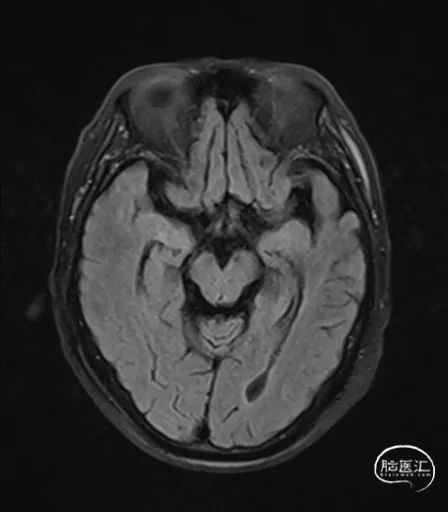

MRI提示小脑缺血性改变。

术后9天MRI: